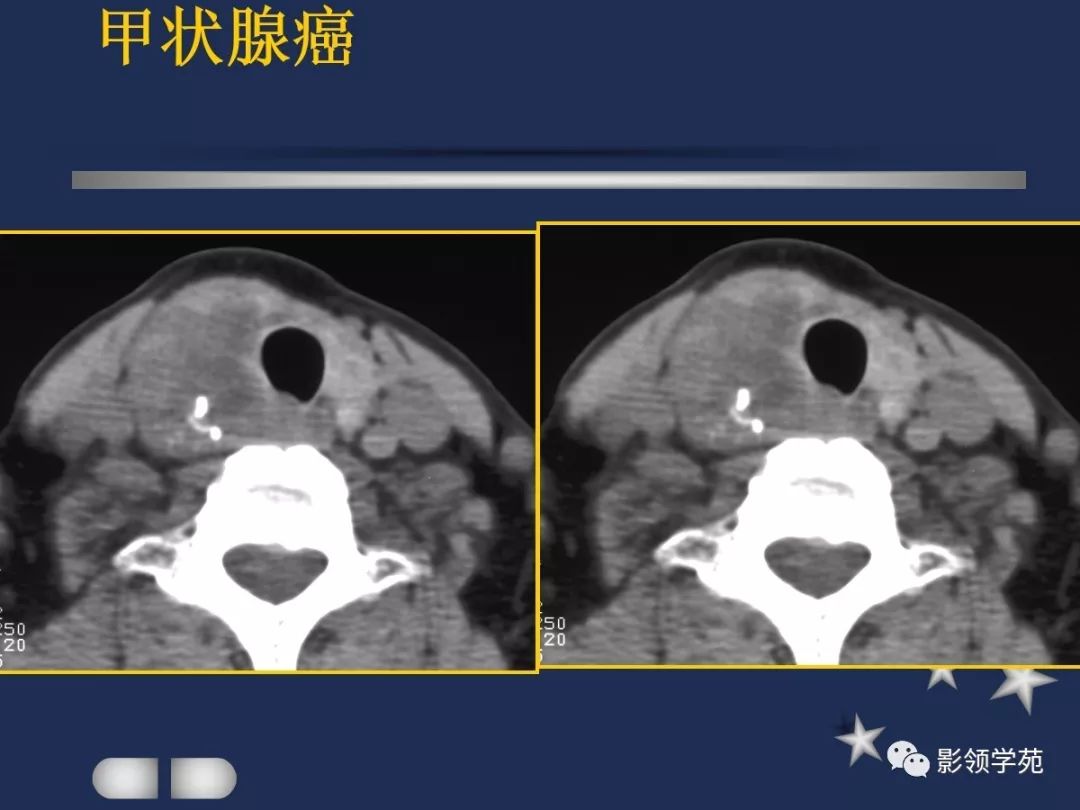

- MRI上实性肿块在T1WI上呈等低信号,在T2WI上呈高信号,囊变区呈长T1长T2信号,钙化在T1WI及T2WI上均呈低信号。

- 甲癌晚期肿瘤常突破甲状腺被膜向周围侵润

- 在增扫时可见环状强化。

- 由于CT和MRI能增强扫描可以清晰显示甲癌的侵润范围和程度,以及显示淋巴结的转移情况

- 手术前分期,指导治疗计划